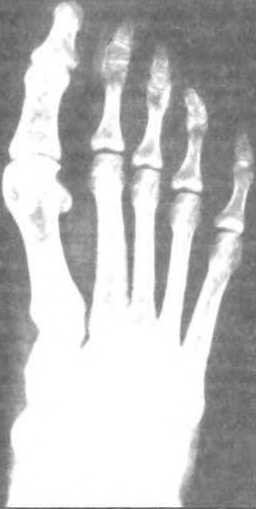

Ил. 78. Утолщение диафиза 2-й плюсны

Утолщение диафиза 2-й и часто 3-й плюсны происходит у 2/3 танцоров обоих полов.

Сверху: рентгеновский снимок правой стопы 15-летней профессиональной танцовщицы: типичное расширение компактного слоя кости 2-ой плюсны. Медуллярная полость сужена. Самое сильное утолщение — в середине кости. Контур кости не отображает патологических изменений. Их нет в суставных поверхностях головки и основания плюсны. Плюсны нормального размера. Внизу: соответствующее схематическое изображение.

Это случается в одинаковой степени и с танцорами, и с танцовщицами, но не имеет отношения к пуантам. Такое утолщение — природная реакция на повышенное и разнообразное использование стопы в танце и ни в коем случае не служит симптомом болезни. Для выполнения необходимых движений стопой важно помнить, что релеве, опускание стоны, совершается в основном голеностопным суставом, а движения поперечно тарзального и клиновидно-плюсневого суставов на 10 — 15° используется минимально.